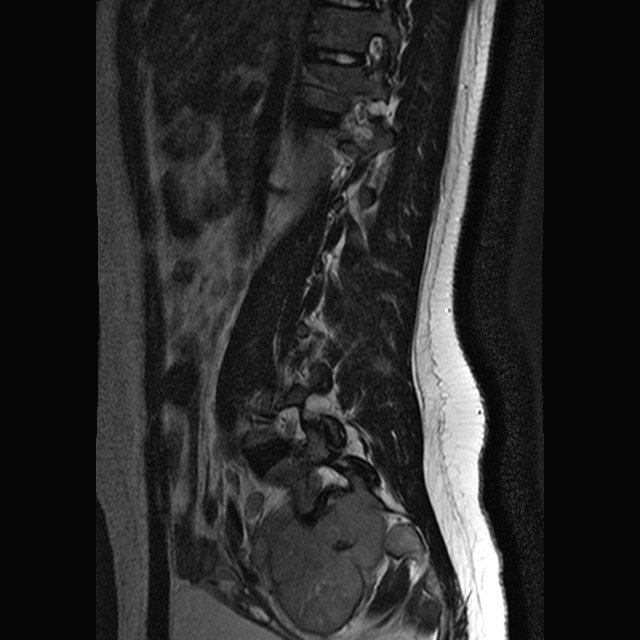

3.    The patient is a 65 year-old man who complained of back pain. On his work up, a 5 cm osteolytic lesion is noted at the sacrum with a midline location and the tumor is roughly symmetrical. The patient has a history of renal cell carcinoma that was removed about 10 years ago. Histoloigic examination of the resected tumor yielded the following images. Which of the following sets of immunohistochemistry and/or molecular testing would allow you to correctly diagnose this tumor? Answer

A.  CD1a, CD163, S100, cytokeratin AE1/AE3.

B.  Isocitrate dehydrogenase 1 and 2 gene (IDH2, IDH2), BRAF mutation and fusion, isochromosome 17.

C.  Pax8, CD10, cytokeratin AE1/AE3.

D.  Synaptophysin, S100, neurofilament.

E.  S100, brachyury, CD10, cytokeratin AE1/AE3.